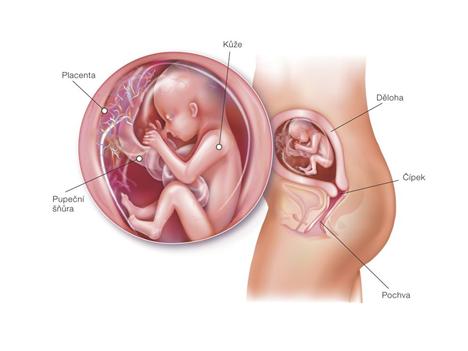

Bohužel se našel mezi mnou a přítelem určitý problém a bez odborné pomoci by jsme se vůbec nedočkali! Snad už se konečně zadařilo a našemu bobískovi, kterého mám v sobě, se bude u nás líbit a vydrží až do samého konce porodu 18.1.2011.